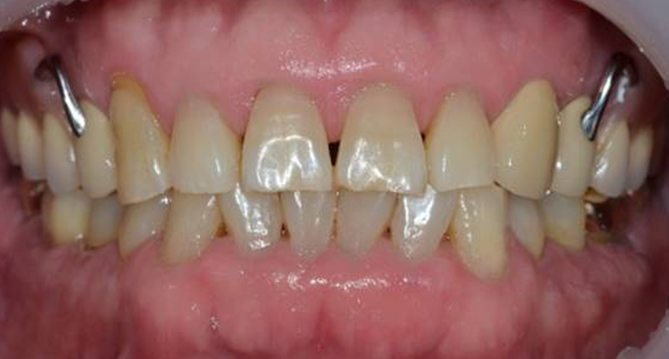

교합과 심미성을 모두 만족시키는

완벽을 추구하는 교정치료를 진행합니다.

풍부한 경험을 보유한 의료진이 직접 상담부터 유지, 치료까지 책임지고

개개인의 구강상태에 따른 적합한 최선의 치료계획을 수립하고 치료합니다.

개인의 얼굴형태나 아래위턱뼈의 형태, 성장발달 단계 등 여러가지를 고려해

치료계획을 세우는 교정은 정밀진단을 통한 올바른 치료가 중요합니다.

클리피씨교정장치

클리피씨교정장치는 치아색과 유사하며,

균등한 힘을 유지해 통증이 적습니다.

초기 교정기간을 단축시켜준다는 장점이 있습니다.